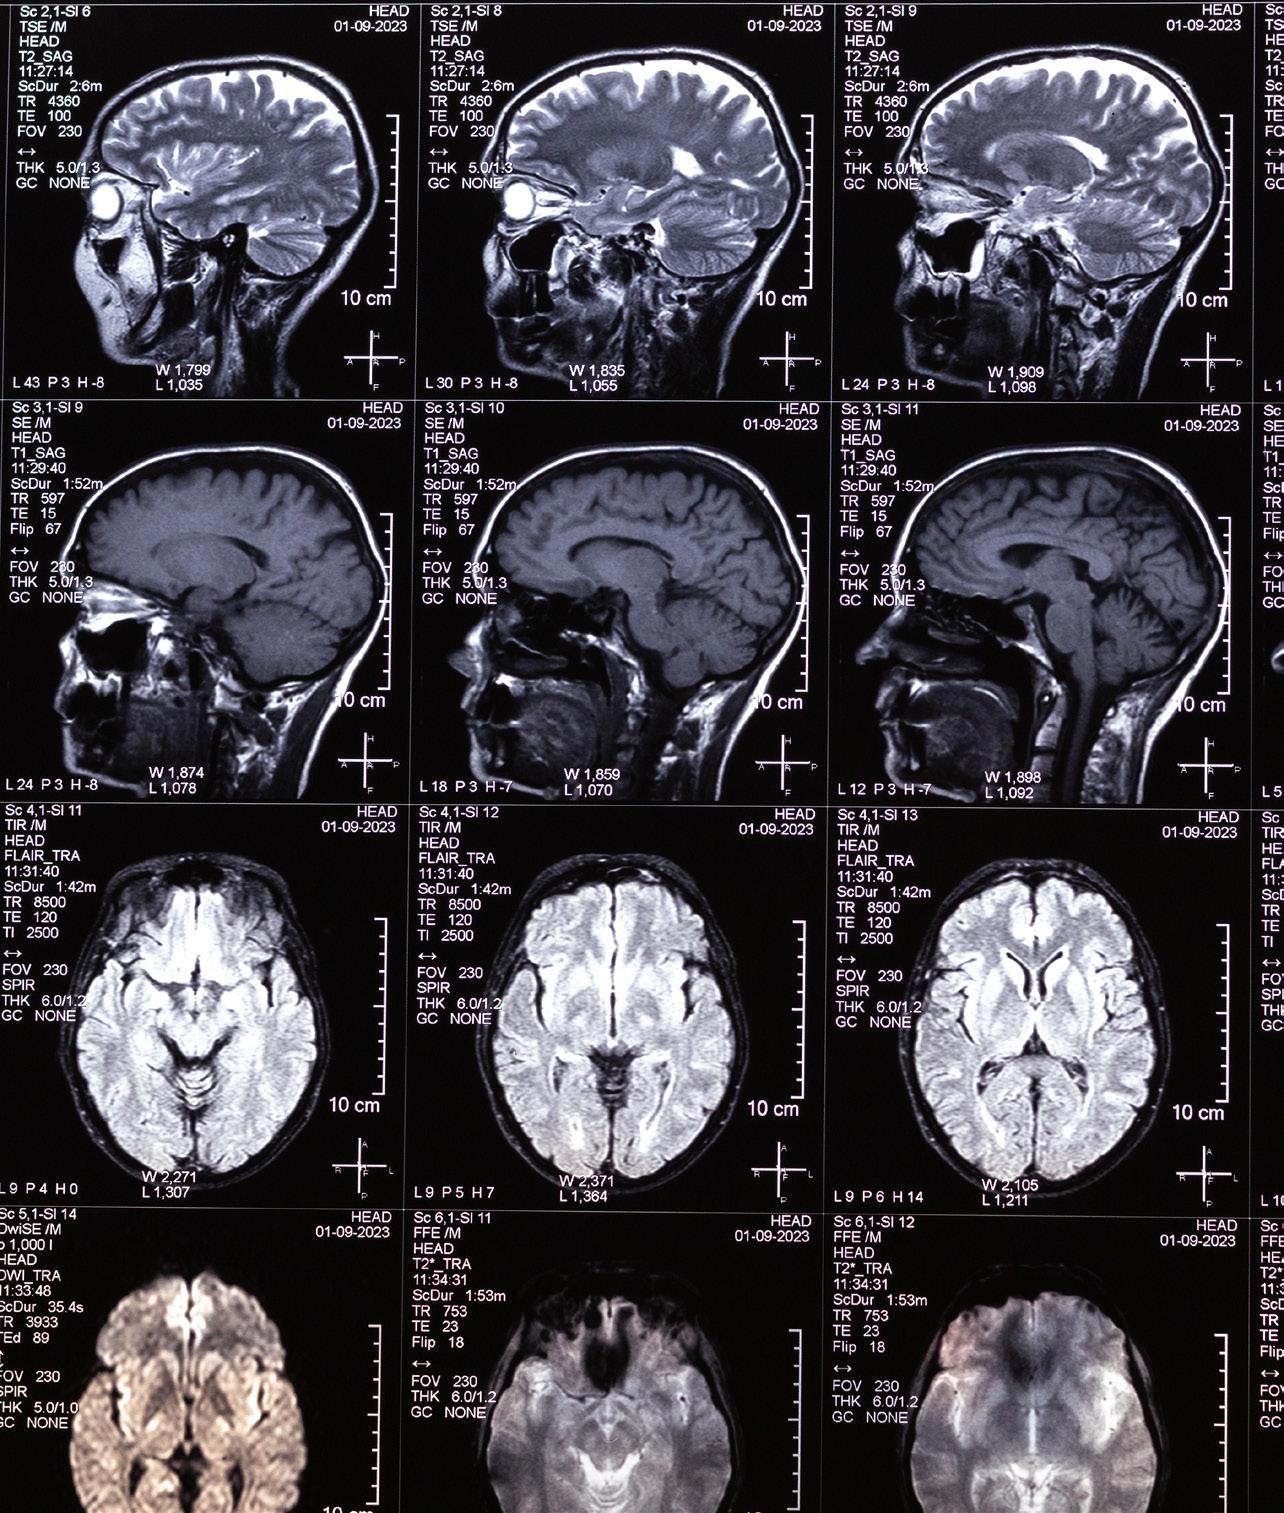

Diagnostic and Interventional Neuroradiology

Full-Time Faculty Complement: 11

• Interpreted all adult and pediatric neuroimaging (CT, MRI); performed image-guided vascular and non-vascular procedures of brain, head and neck, and spine

• Provided daily extended services throughout evening and overnight (24/7/365)

• Participated in multiple weekly multidisciplinary clinical care team conferences

• Continued to provide teleradiological coverage for community radiology professional services contract with HCA/Frankfort Regional Medical Center